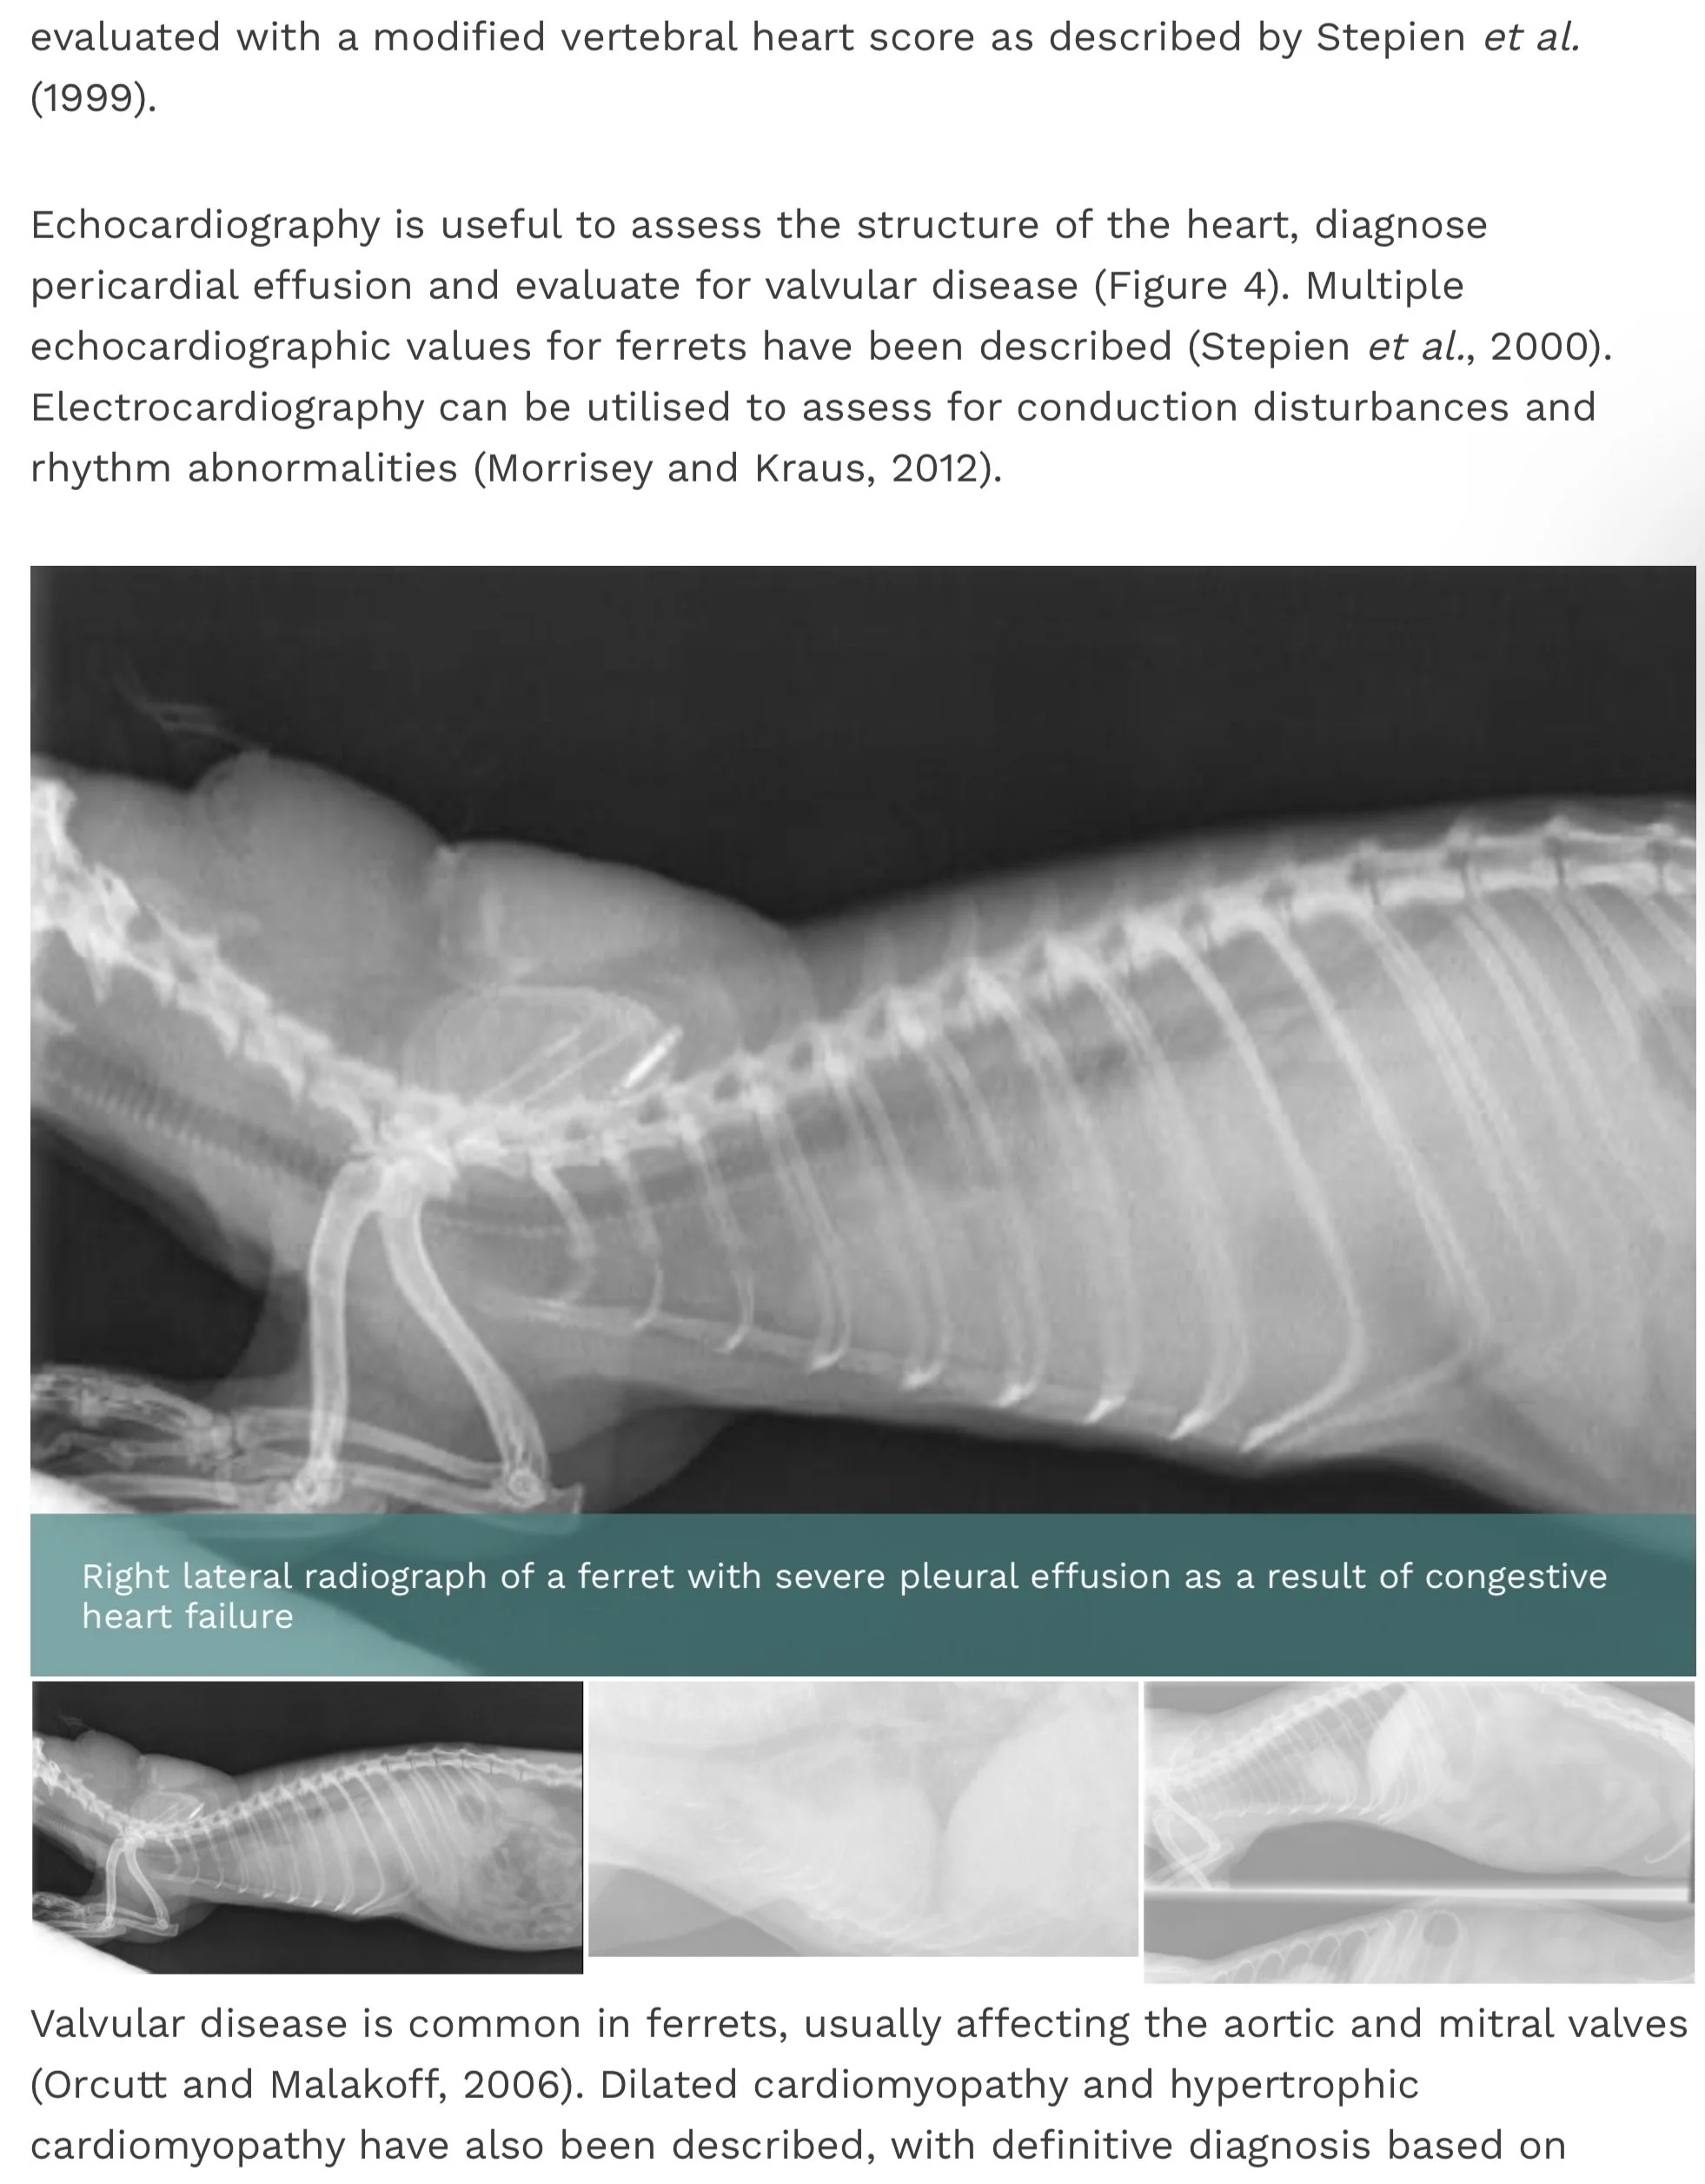

Cardiac / Heart Issues MEDICAL 15 Dec Written By Jen Herd Source - Improve Veterinary Practice Jen Herd